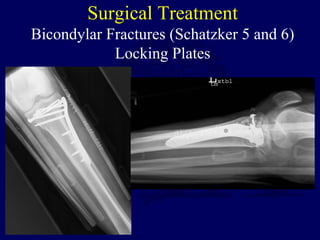

Bicondylar Fractures (Schatzker 5 and 6)

Locking Plates

Surgical Treatment